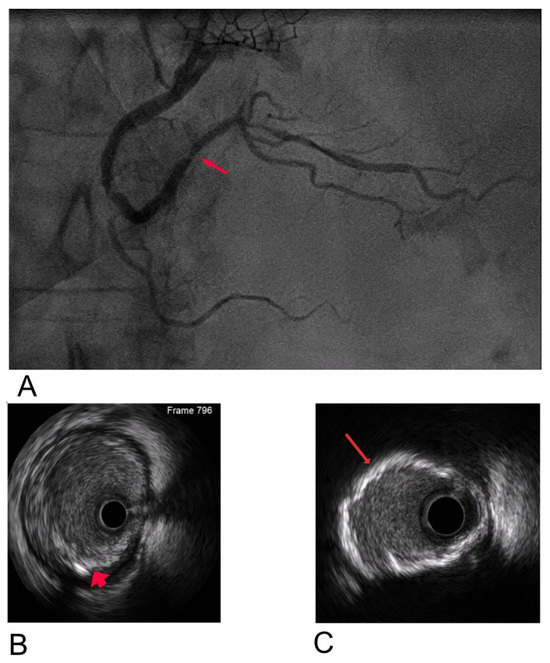

Case Report

Endocardial Ablation of Atrial Flutter with Involvement of the Vein of Marshall: A Case Report

by Lucio Addeo, Konstantinos Triantafyllou, Hellen Dockx, Monika Shumkova, Antonio Rapacciuolo, Stefano Nardi, Vittoria Marino, Luigi Argenziano, Pasquale Guarini, Laura Adelaide Dalla Vecchia, Francesco Donatelli and Tom De Potter

Background: Atypical atrial flutter (AFL) is a complex clinical challenge, particularly in patients with prior atrial fibrillation (AF) treated with pulmonary vein isolation (PVI). Arrhythmias involving the vein of Marshall (VOM) often require extensive lesion sets, including ethanol infusion, to effectively target the [...] Read more.

Background: Atypical atrial flutter (AFL) is a complex clinical challenge, particularly in patients with prior atrial fibrillation (AF) treated with pulmonary vein isolation (PVI). Arrhythmias involving the vein of Marshall (VOM) often require extensive lesion sets, including ethanol infusion, to effectively target the epicardial substrate. To minimize tissue damage, an alternative strategy has been proposed, emphasizing advanced electroanatomical mapping, entrainment maneuvers, and highly targeted ablation techniques. Case Presentation: We describe a 72-year-old woman with recurrent atrial arrhythmias following pulmonary vein isolation (PVI), who presented with palpitations as her primary symptom. After ineffective pharmacological therapy, she underwent a catheter ablation procedure. Electroanatomical mapping revealed significant left atrial scarring and suggested a macroreentrant circuit involving the VOM. Entrainment maneuvers confirmed the VOM’s involvement. A single targeted endocardial ablation guided by the ablation index terminated the arrhythmia within 12 s, without the need for ethanol infusion or extensive lesion sets. Discussion: This case underscores the VOM’s role in sustaining atypical AFL post-PVI and highlights the effectiveness of precise electroanatomical mapping combined with targeted endocardial ablation. Unlike broader ablation or ethanol infusion strategies, a focused lesion at the critical isthmus achieved arrhythmia termination with minimal tissue damage. Conclusions: Endocardial ablation at the site of entrainment can safely and effectively treat VOM-related AFL, offering symptom relief and restoration of sinus rhythm. This approach may reduce procedural risks and expand the feasibility of VOM-related arrhythmia management in centers without access to ethanol infusion. Full article